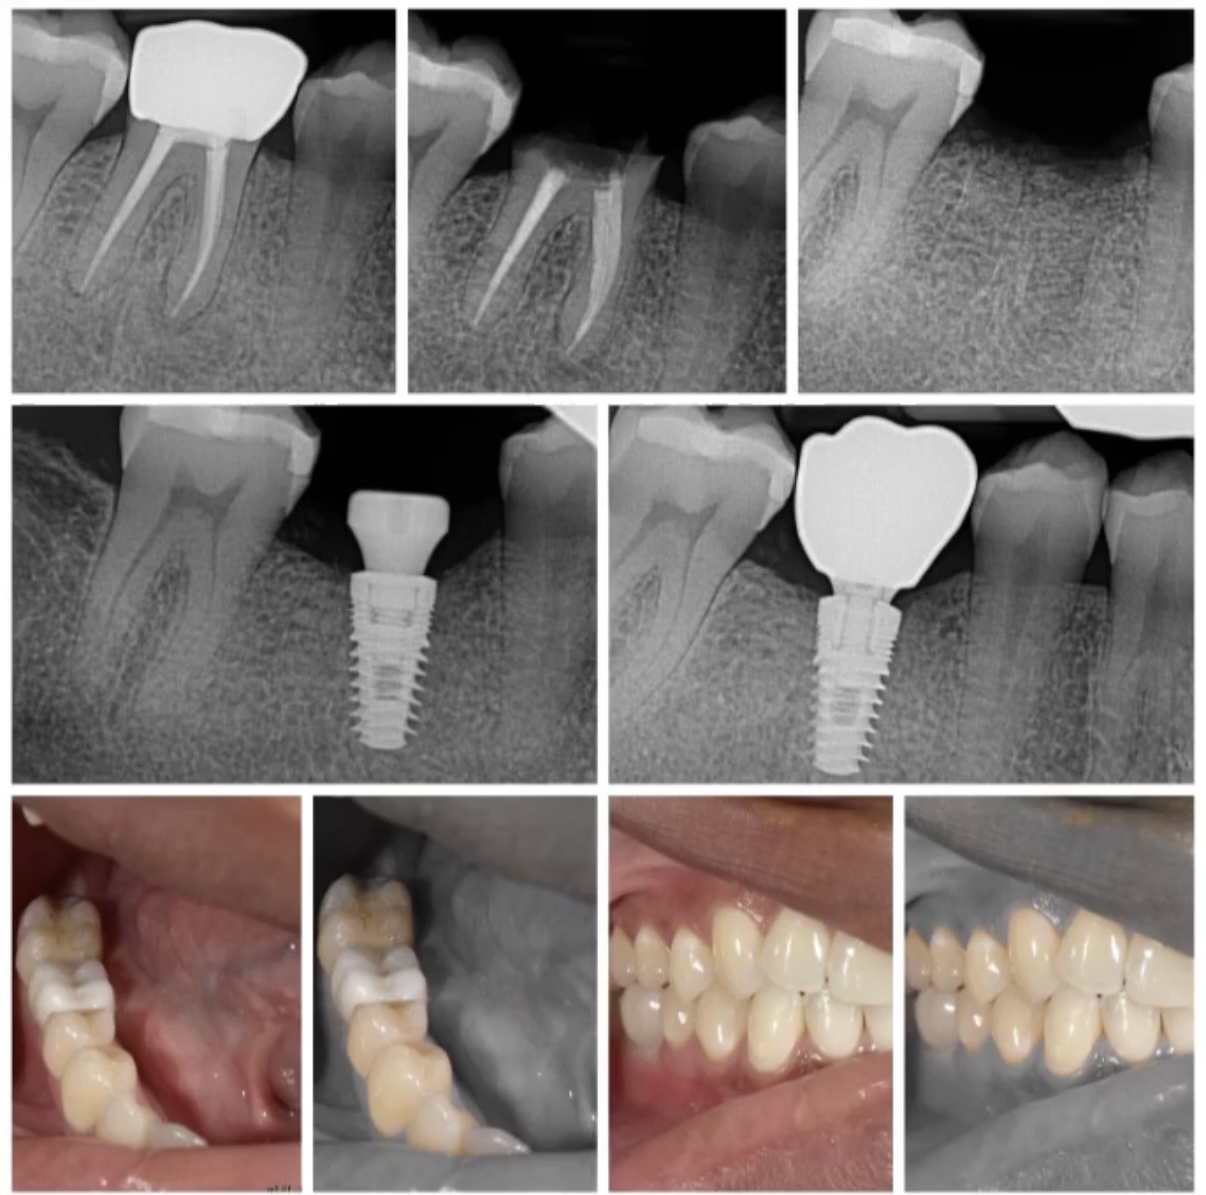

My dental office is located in Bloomfield hills Michigan, Bloomfield hills dental associates. I provide all aspects of dentistry, from braces, fillings, and extractions. But my main focus is cosmetic and implant dentistry. What sets me apart is my compassion for my patients needs and the ability to provide and deliver their dream results. Having an artistic mind allows me to show what each individual can expect before they even begin their transformations.